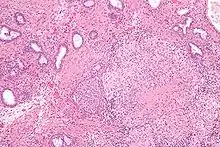

![]() Microscopic image of the Calmette-Guérin bacillus, Ziehl–Neelsen stain, magnification: 1,000nn | |